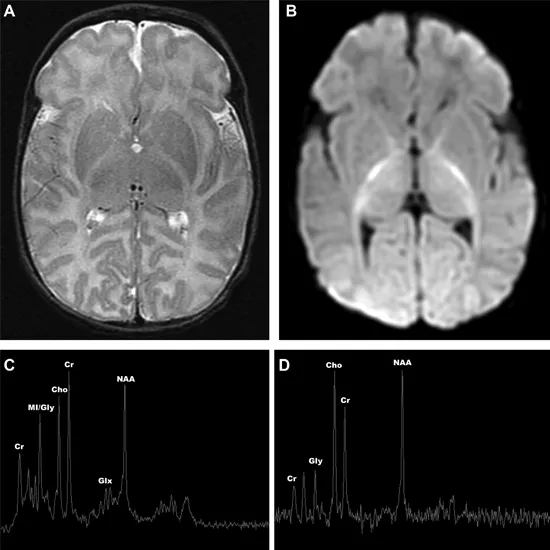

MRI MRI Spectroscopy Prostate is used to identify the anatomical location of a tumor. This examination compares the chemical composition of normal brain tissue.

MRI Spectroscopy Prostate is a non-invasive diagnostic test used to measure the biochemical changes in the brain. The procedure is specially done to check the presence of tumors and detect tissue changes in stroke and epilepsy.